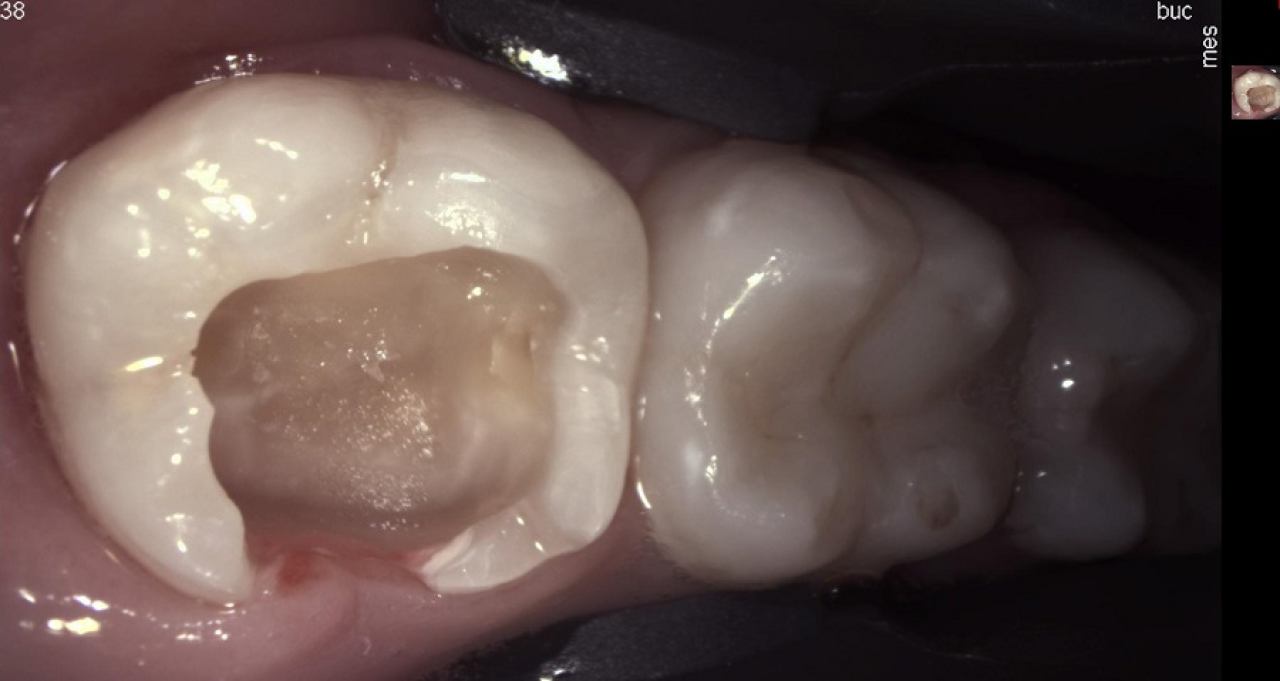

Parodontologija i kirurgija

Parodontologija je grana dentalne medicine koja se bavi zdravljem potpornih struktura zuba (parodonta). Parodont se sastoji od zubnog mesa (gingiva), kosti i vlakana koja vežu zub za kost (parodontalni ligament).

Ovo je grana kojoj Marković Dental Clinic pridaje puno pažnje jer je vrlo kompleksna i bitna za cijelo oralno zdravlje.

Marković Dental Clinic svojim pacijentima omogućuje oralno kirurške zahvate u vrhunski opremljenoj kirurškoj ordinaciji pod strogo kontroliranim uvjetima sterilnosti. Svi zahvati se rade u lokalnoj anesteziji i potpuno su bezbolni.

Najčešći zahvat u oralnoj kirurgiji je ekstrakcija (vađenje) zuba, a drugi oralno kirurški zahvati su apikotomija (amputacija vrška korijena zuba) i alveotomija (vađenje umnjaka).